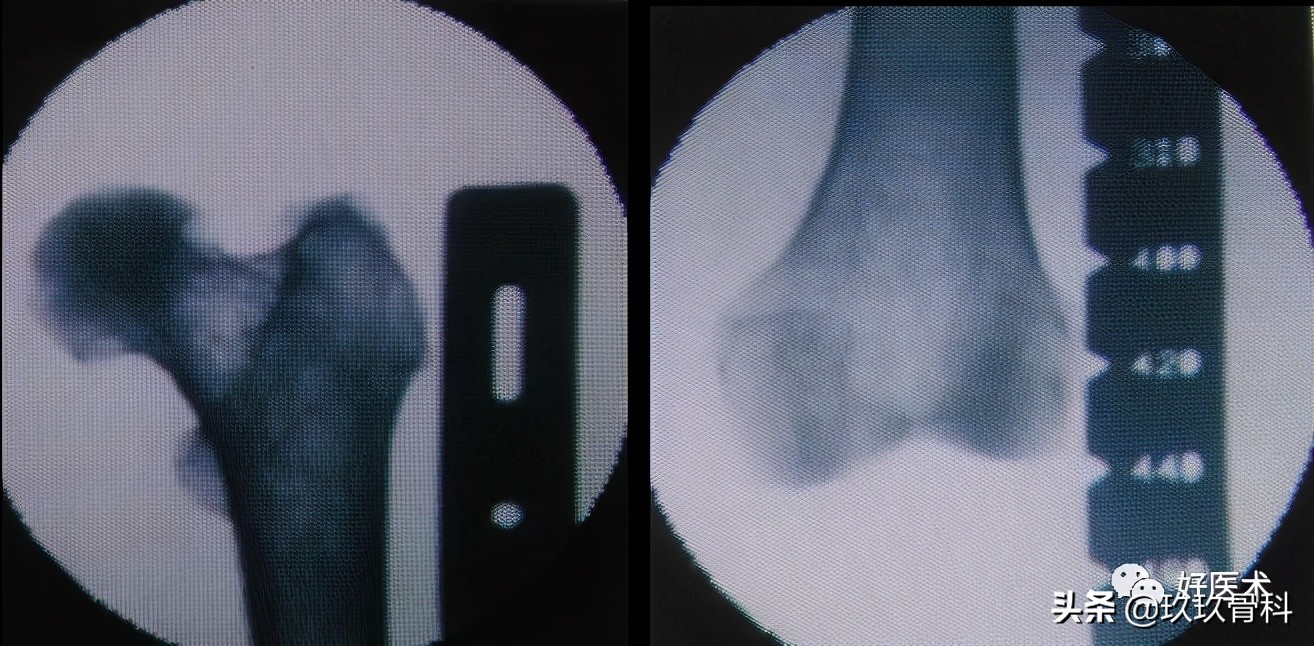

股骨髓内钉插入技术

1)顺行股骨髓内钉进针点

部位:

- 梨状窝

- 梨状窝后外侧

2)顺行股骨髓内钉进针点的准备

- 髋关节屈曲内收

- 大粗隆近端纵切口(不能太靠后)

- 安放导针

- 安放软组织保护挡板

3)逆行股骨髓内钉进针点

- 屈膝30°

- 导针长轴与股骨干远段髓腔方向一致

- 经髌韧带通过保护套筒插入克氏针到远端股骨

--正位-股骨髁间窝中间注意

--侧位-Blumensaat's 线尖端

- 毋伤PCL起点